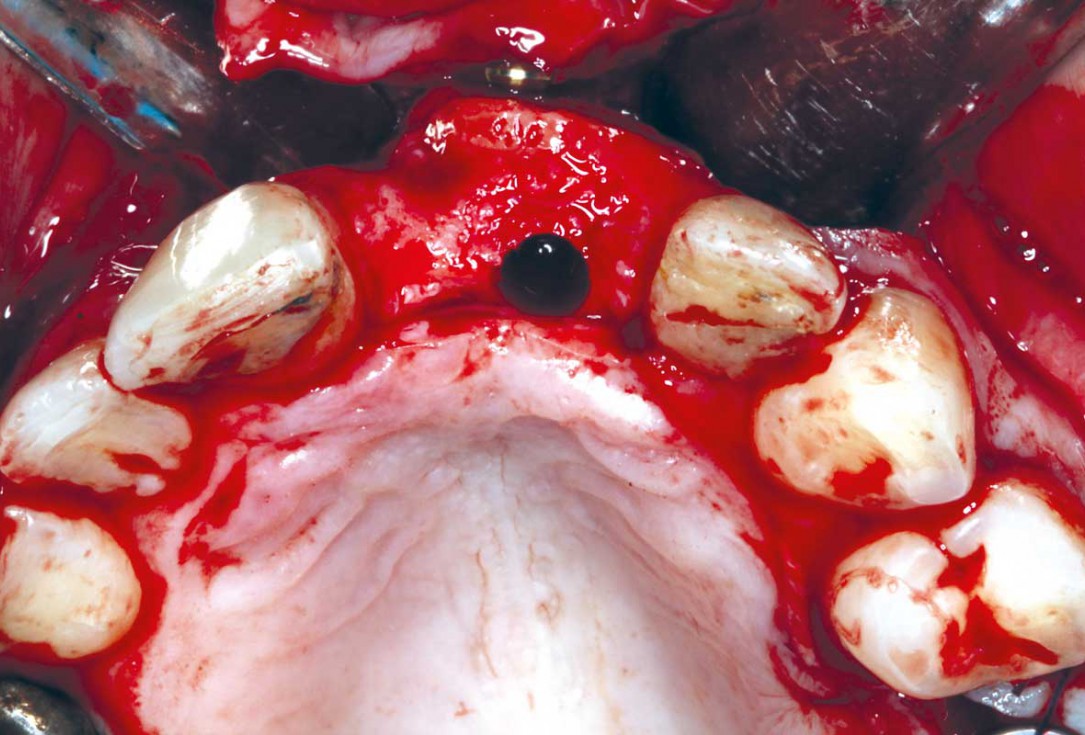

5/35 - Three-sided full thickness flap and cleaning the surgical area from the granulation tissueBlock grafting in the aesthetic zone with maxgraft®, Jason® membrane and cerabone® - Dres. H. Maghaireh and V. Ivancheva

6/35 - Three-sided full thickness flap and cleaning the surgical area from the granulation tissueBlock grafting in the aesthetic zone with maxgraft®, Jason® membrane and cerabone® - Dres. H. Maghaireh and V. Ivancheva